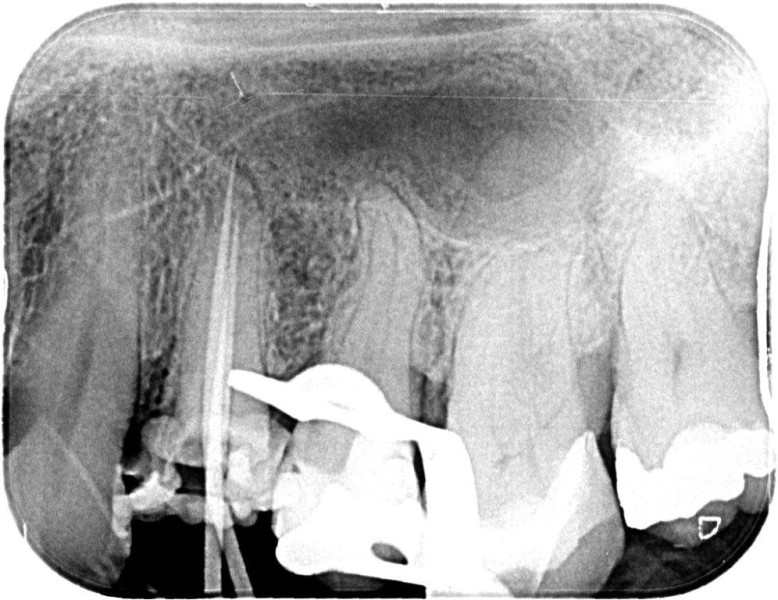

Re-treatments are more difficult than primary root canal work as the filling material has to be removed and any errors in the previous treatment corrected where possible.

Post removal cases